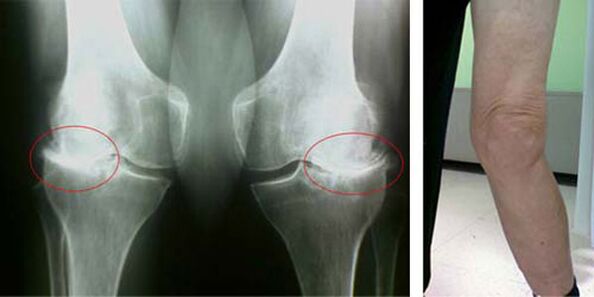

In a healthy knee joint, cartilage is a lining that does not allow bone contact, thus eliminating the possibility of injury while walking. The diseased cartilage cannot cope with this function, so the joints show signs of stiffness and pain during movement. Due to internal pathological changes, the condition becomes permanent when the thinning of cartilage tissue causes the bone to thicken and create conditions for the appearance of bone spurs - osteophytes, which can cause acute pain.

The initial stages of pathology such as knee arthropathy are not visually manifested in any way. However, over time, the patient will notice signs of knee deformity, as well as characteristic bending (inward) along the axis of the lower leg. Crunch also occurs when you need to bend your leg.

The presence of pain, limited movement of the knee makes a person see a doctor and get checked. To do this, he needs to pass tests and have X-rays of the diseased joints. Magnetic resonance imaging is performed if these measures are insufficient to confirm arthropathy of the knee. Based on the data collected, the doctor chooses the best treatment.